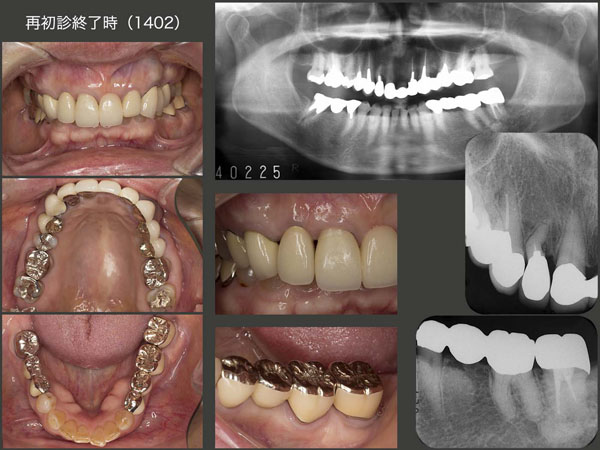

2014年2月,今回の一連の治療が一段落ついた時の状態.移植した右上2および左下7は,問題なく経過している.今後も咬合力が強いことから歯根破折が生じる可能性が懸念されるので,日中のTCH,咀嚼時に少しだけ力を抜くことを常に意識するようにお願いしている.